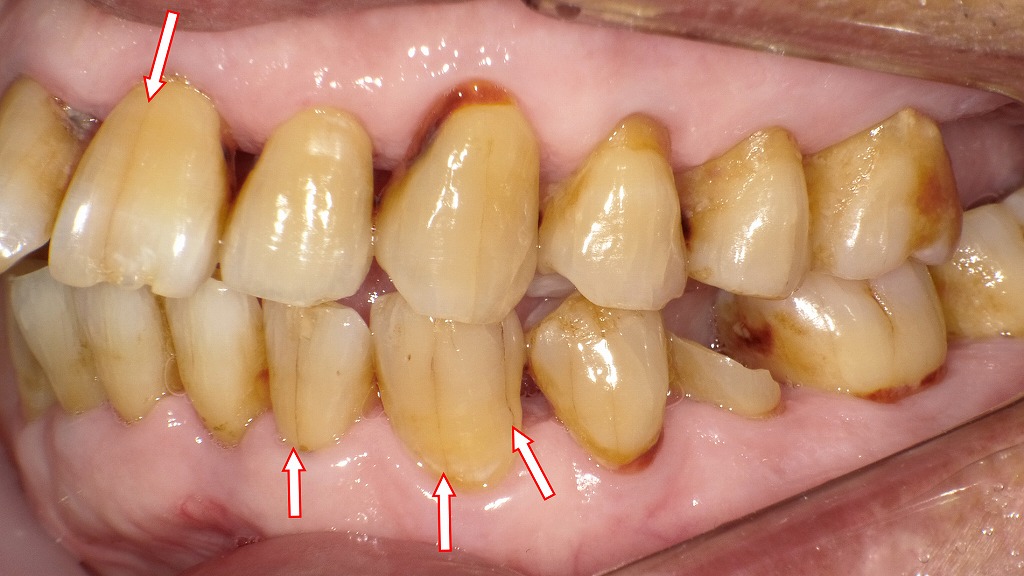

マイクロクラックの症例

この画像は、歯の表面に生じたマイクロクラック(歯のヒビ)を示しています。赤い矢印の部分に注目してください。

🔍 観察される特徴

- 矢印の位置に、エナメル質表面に細い線状のヒビ(マイクロクラック)が確認できます。

- これらは歯の表面(エナメル質)に限局した微細な亀裂で、内部の象牙質までは達していません。

- 光の反射で白く・透明な線のように見えるのが特徴です。

🦷 マイクロクラックの主な原因

- 噛みしめ・食いしばり(ブラキシズム)

強い咬合力が歯に集中し、表面に微細なヒビが生じます。 - 加齢変化

長年の使用により、エナメル質が硬くもろくなり発生します。 - 急激な温度変化

熱い飲み物・冷たい飲み物を繰り返し摂取することで、歯が膨張・収縮しヒビが入ります。 - 外傷や硬いものの咬みすぎ

硬い食べ物(氷・ナッツなど)を噛んだり、転倒などで衝撃を受けた場合。